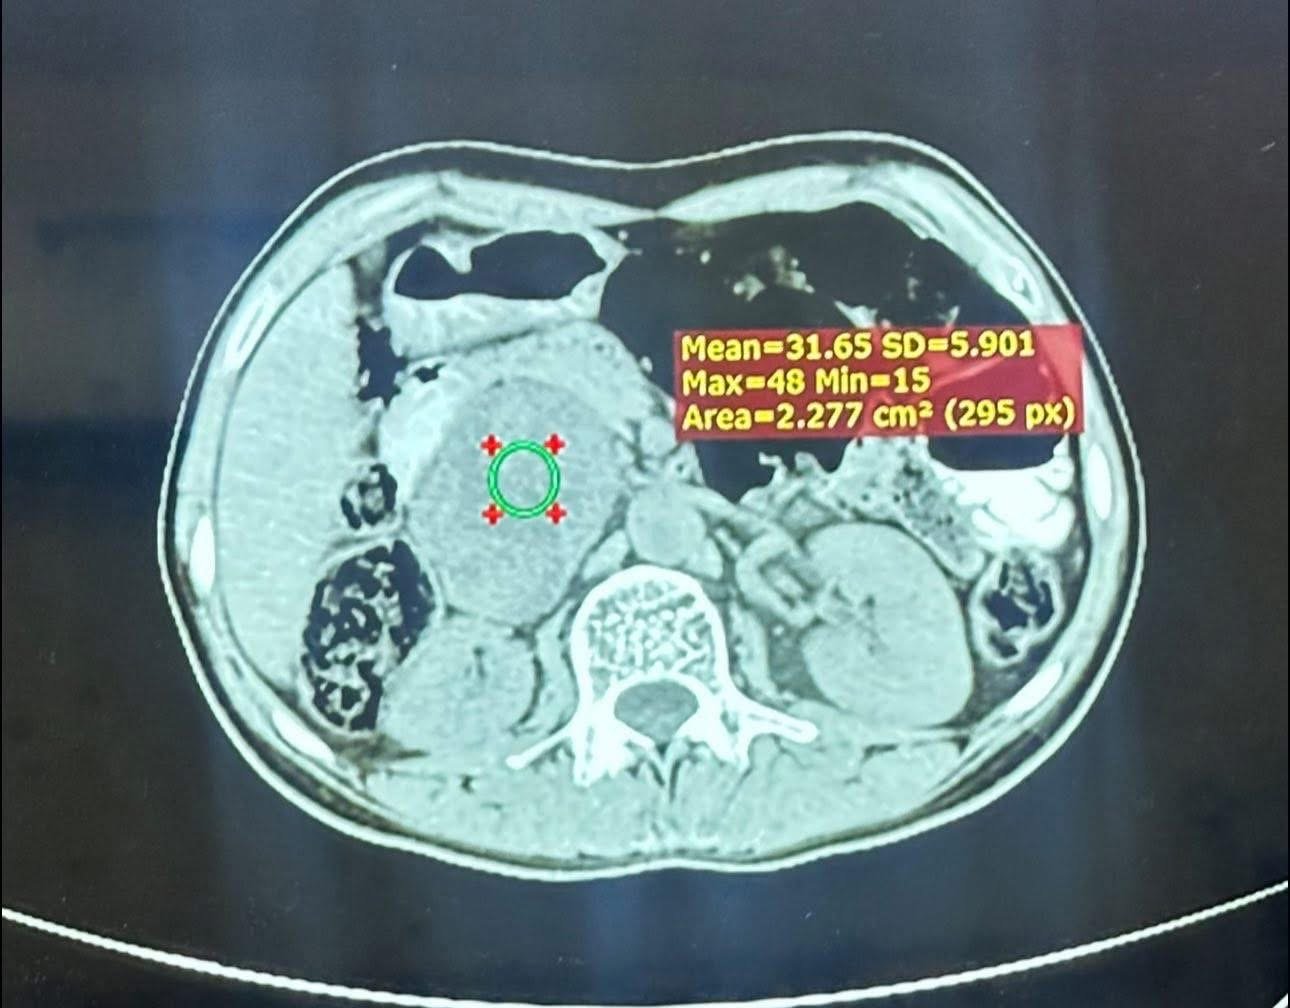

المريض، البالغ من العمر ٢٥ عامًا ومن سكنة محافظة نينوى / الموصل، أُحيل إلى مركز الفيحاء التخصصي بعد معاناة طويلة من ارتفاع شديد في ضغط الدم وتسارع حاد في ضربات القلب. وبعد إجراء الفحوصات اللازمة، تبيّن وجود ورم كبير في الغدة الكظرية اليمنى، يفرز كميات مرتفعة جدًا من هرمون الأدرينالين (Pheochromocytoma)، ما شكّل خطرًا كبيرًا على حياته. كما أظهرت الفحوصات أن الورم كان مخترقًا من الأوعية الدموية الرئيسية، مما زاد من تعقيد وخطورة التداخل الجراحي.

ويُعد هذا الورم أكبر ورم كظري يفرز هورمون الادرينالين تم التعامل معه من حيث الحجم.